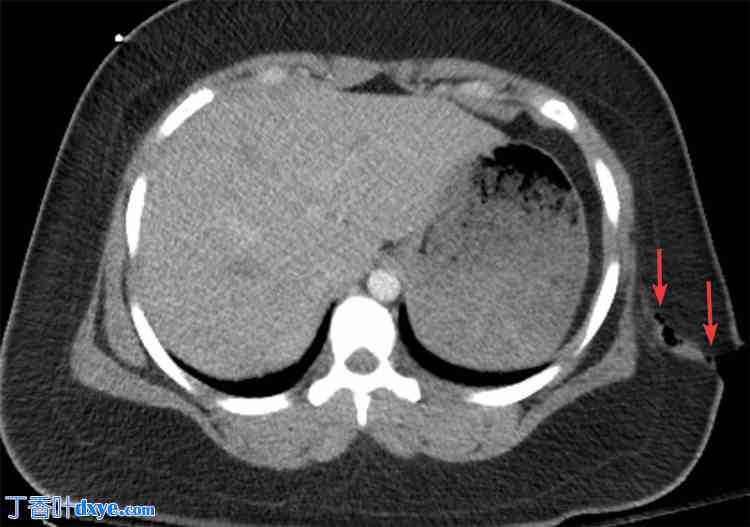

图 3. 增强 CT 扫描,左侧腹部肌肉穿透性伤口轴向视图,伤口进入腹膜,伴有大网膜疝出。

3.jpg

疝出的大网膜用箭头标记。